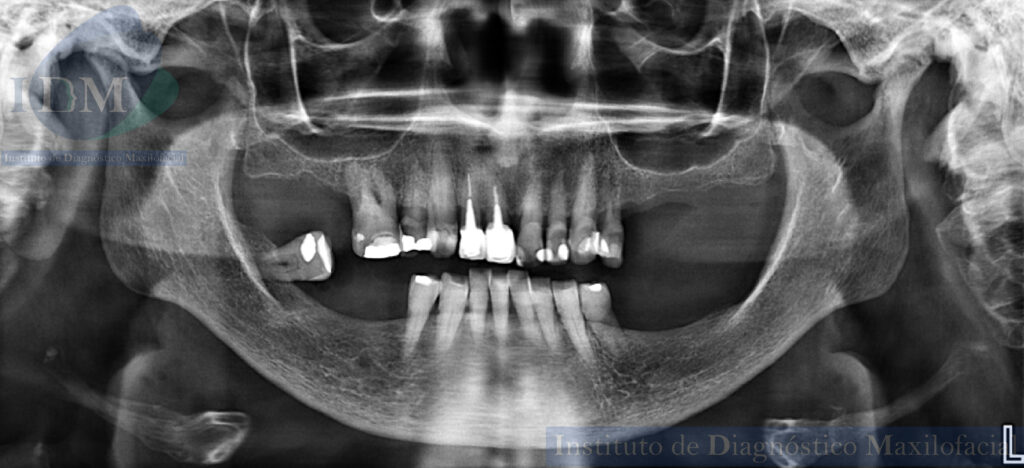

Al observar la radiografía panorámica se aprecia, el aplanamiento del contorno condilar bilateral, la neumatización de ambos senos maxilares, edentulismo parcial de ambos maxilares, múltiples piezas dentarias con restauraciones coronarias. Piezas 12-11 con coronas protésicas, espigos intrarradiculares y obturación de conducto, asimismo se observa la reabsorción ósea del proceso alveolar.

Radiografia Panorámica